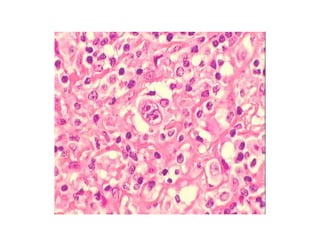

• Biopsie exérèse ganglionnaire avec envoi du

prélèvement frais au laboratoire

d’anatomopathologie pour examen

anatomopathologique et immunohistochimique.

En général, on demande aussi une analyse

cytogénétique et de biologie moléculaire.

2) Quel examendemandez vous pour confirmer le diagnostic ? • Biopsie exérèse ganglionnaire avec envoi du prélèvement frais au laboratoire d’anatomopathologie pour examen anatomopathologique et immunohistochimique. En général, on demande aussi une analyse cytogénétique et de biologie moléculaire.